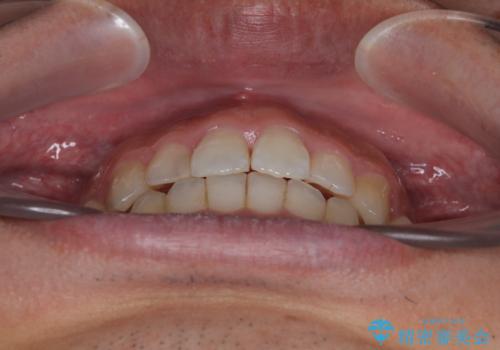

前歯のデコボコと突出感をマウスピース矯正できれいに

- 上下前歯のデコボコと突出感を気にして来院された患者様です。

目立たない装置を希望されたため、インビザラインによるマウスピース矯正を行うこととしました。

矯正治療後に銀歯をセラミックに替えたいとの要望があり、概ね歯列が整ったところで銀歯をセラミックに替え、仕上げにインビザライン1セットを使用して最終的に歯列を整えました。